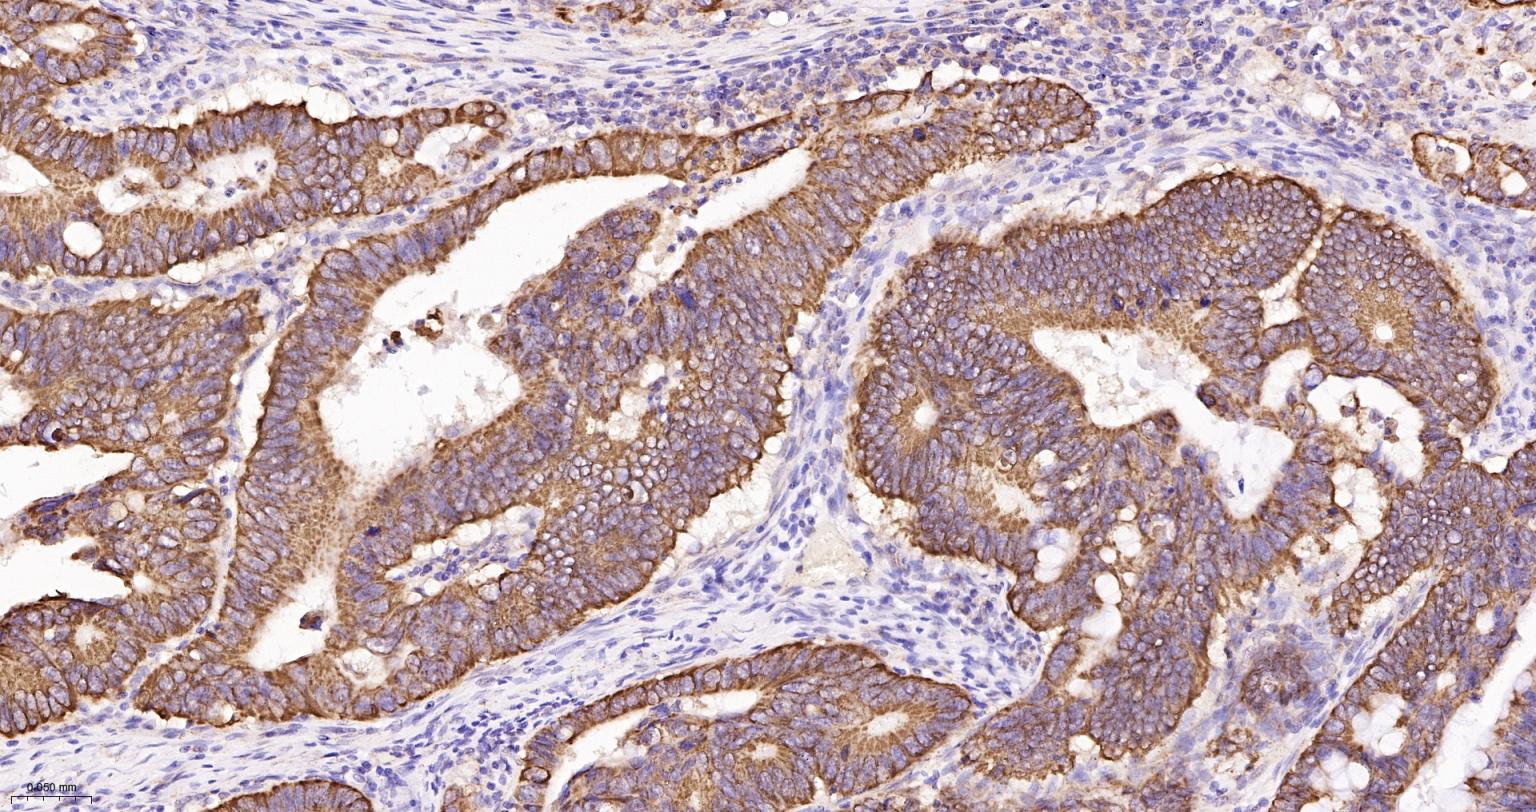

Paraformaldehyde-fixed, paraffin embedded Human Endometrial Cancer; Antigen retrieval by boiling in sodium citrate buffer (pH6.0) for 15 min; The section was incubated with AIF Monoclonal Antibody, Unconjugated (bsm-34316R) at 1:200 overnight at 4°C, followed by conjugation to the bs-0295G-HRP and DAB (C-0010) staining.

Paraformaldehyde-fixed, paraffin embedded Human Colon Cancer; Antigen retrieval by boiling in sodium citrate buffer (pH6.0) for 15 min; Antibody incubation with AIF Monoclonal Antibody, Unconjugated(bsm-34316R) at 1:200 overnight at 4°C, followed by conjugation to the SP Kit(Rabbit, SP-0023) and DAB (C-0010) staining.